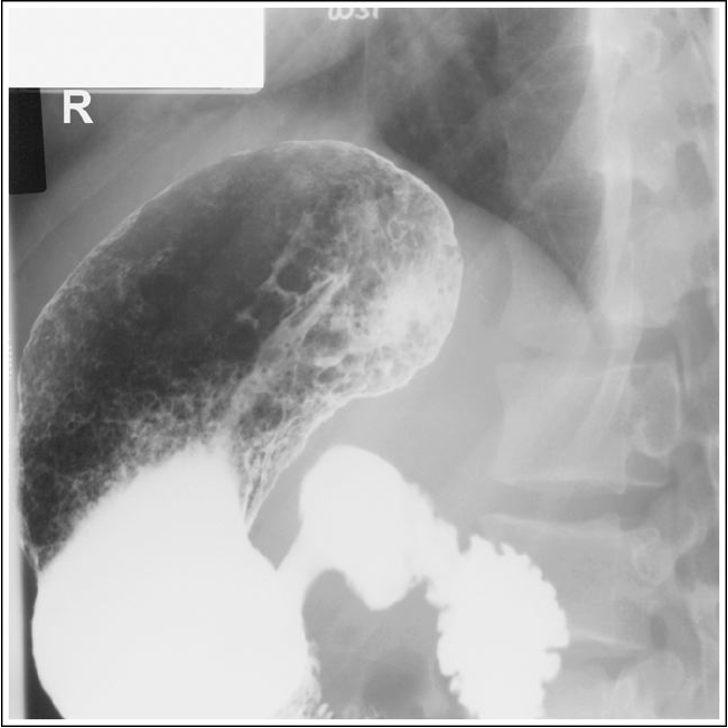

Lateral stomach descending duodenum is partially superimposed over the duodenal bulb and vertebrae, and the posterior surfaces of the thoracic and lumbar vertebrae are not superimposed. Patient was not in a true lateral position